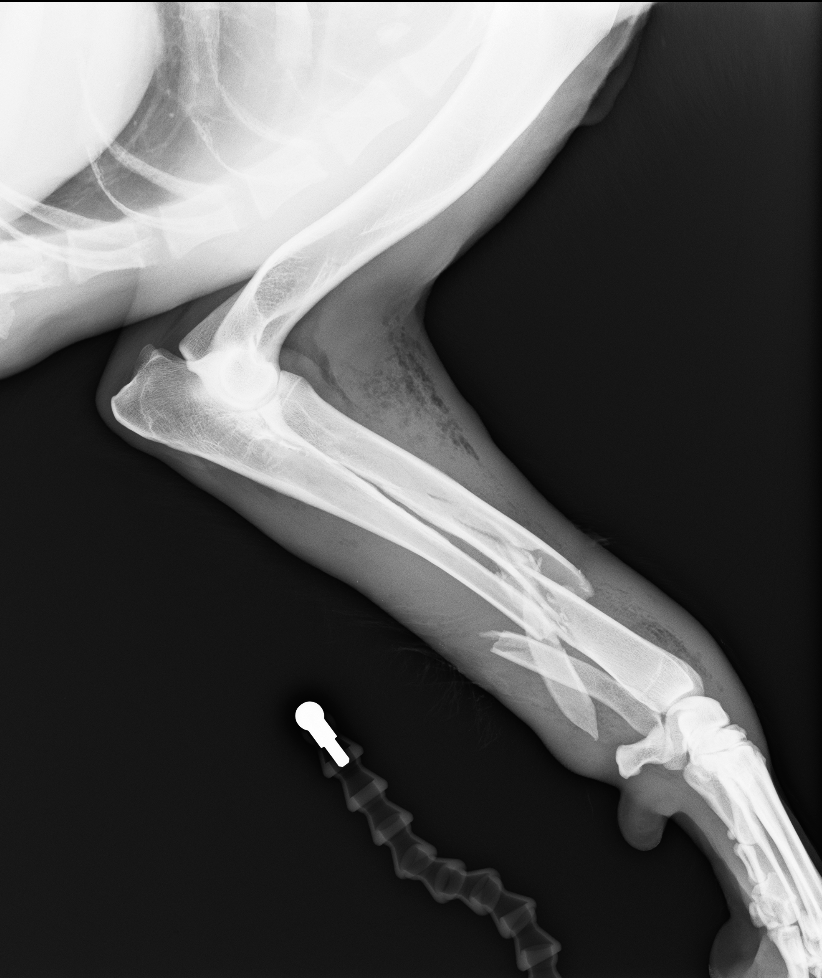

左前肢挙上し、軟部組織の腫脹が認められました。レントゲン、CT検査より橈骨・尺骨の粉砕骨折が認められました

診断と治療

左橈骨・尺骨の粉砕、解放骨折と診断し、橈骨にはLCPのダブルプレート、尺骨には髄内ピンによる治療を行いました

before